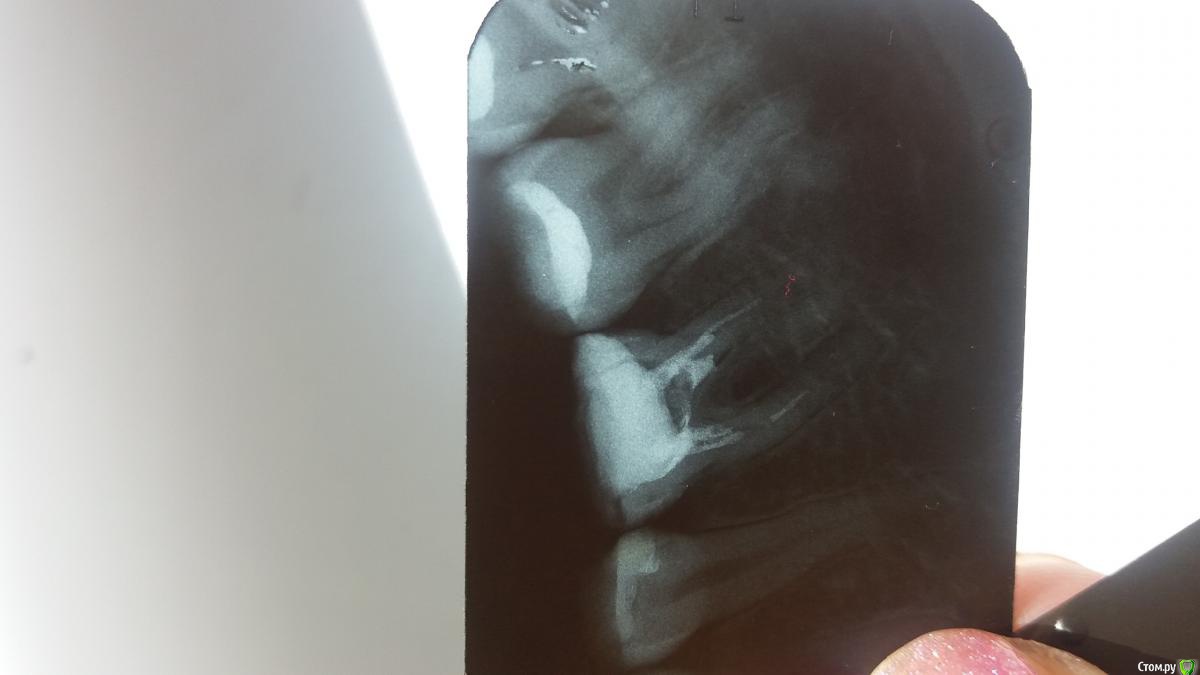

Анна Л Опубликовано 2 мая, 2018 Поделиться Опубликовано 2 мая, 2018 (изменено) Первый раз в 2016 году лечили мне зуб с пломбировкой каналов. Снимок номер 1. Неделю назад переплобмировали мне каналы, врач оставила там интсрумент. Снимок тоже прилагаю. Направила к доктору лечить под микроскопом. Он не смог достать интсрумент и сказал что не прошел все каналы, это невозможно и сделал все что мог и залил каналы горячей гуттаперча и врменной пломбой. Через 3 для пошла на процедуру подгтовие вкладки, снова временная пломба. И вот на след день у меня начал ныть зуб,температура 37, немного опухла щека, ночью сплю зуб не беспокоит, а вот днем все та же ноющая боль и боль как будто до уха доходит. Пью третий день порошок Нимесил, 2 раза в сутки. Боль моя и не увеличивается и не ументшается. Врач говорит дальше пить Нимесил.Первый раз в 2016 году лечили мне зуб с пломбировкой каналов. Снимок номер 1. Неделю назад переплобмировали мне каналы, врач оставила там интсрумент. Снимок тоже прилагаю. Направила к доктору лечить под микроскопом. Он не смог достать интсрумент и сказал что не прошел все каналы, это невозможно и сделал все что мог и залил каналы горячей гуттаперча и врменной пломбой. Через 3 для пошла на процедуру подгтовие вкладки, снова временная пломба. И вот на след день у меня начал ныть зуб,температура 37, немного опухла щека, ночью сплю зуб не беспокоит, а вот днем все та же ноющая боль и боль как будто до уха доходит. Пью третий день порошок Нимесил, 2 раза в сутки. Боль моя и не увеличивается и не ументшается. Врач говорит дальше пить Нимесил. Изменено 2 мая, 2018 пользователем Анна Л Ссылка на комментарий